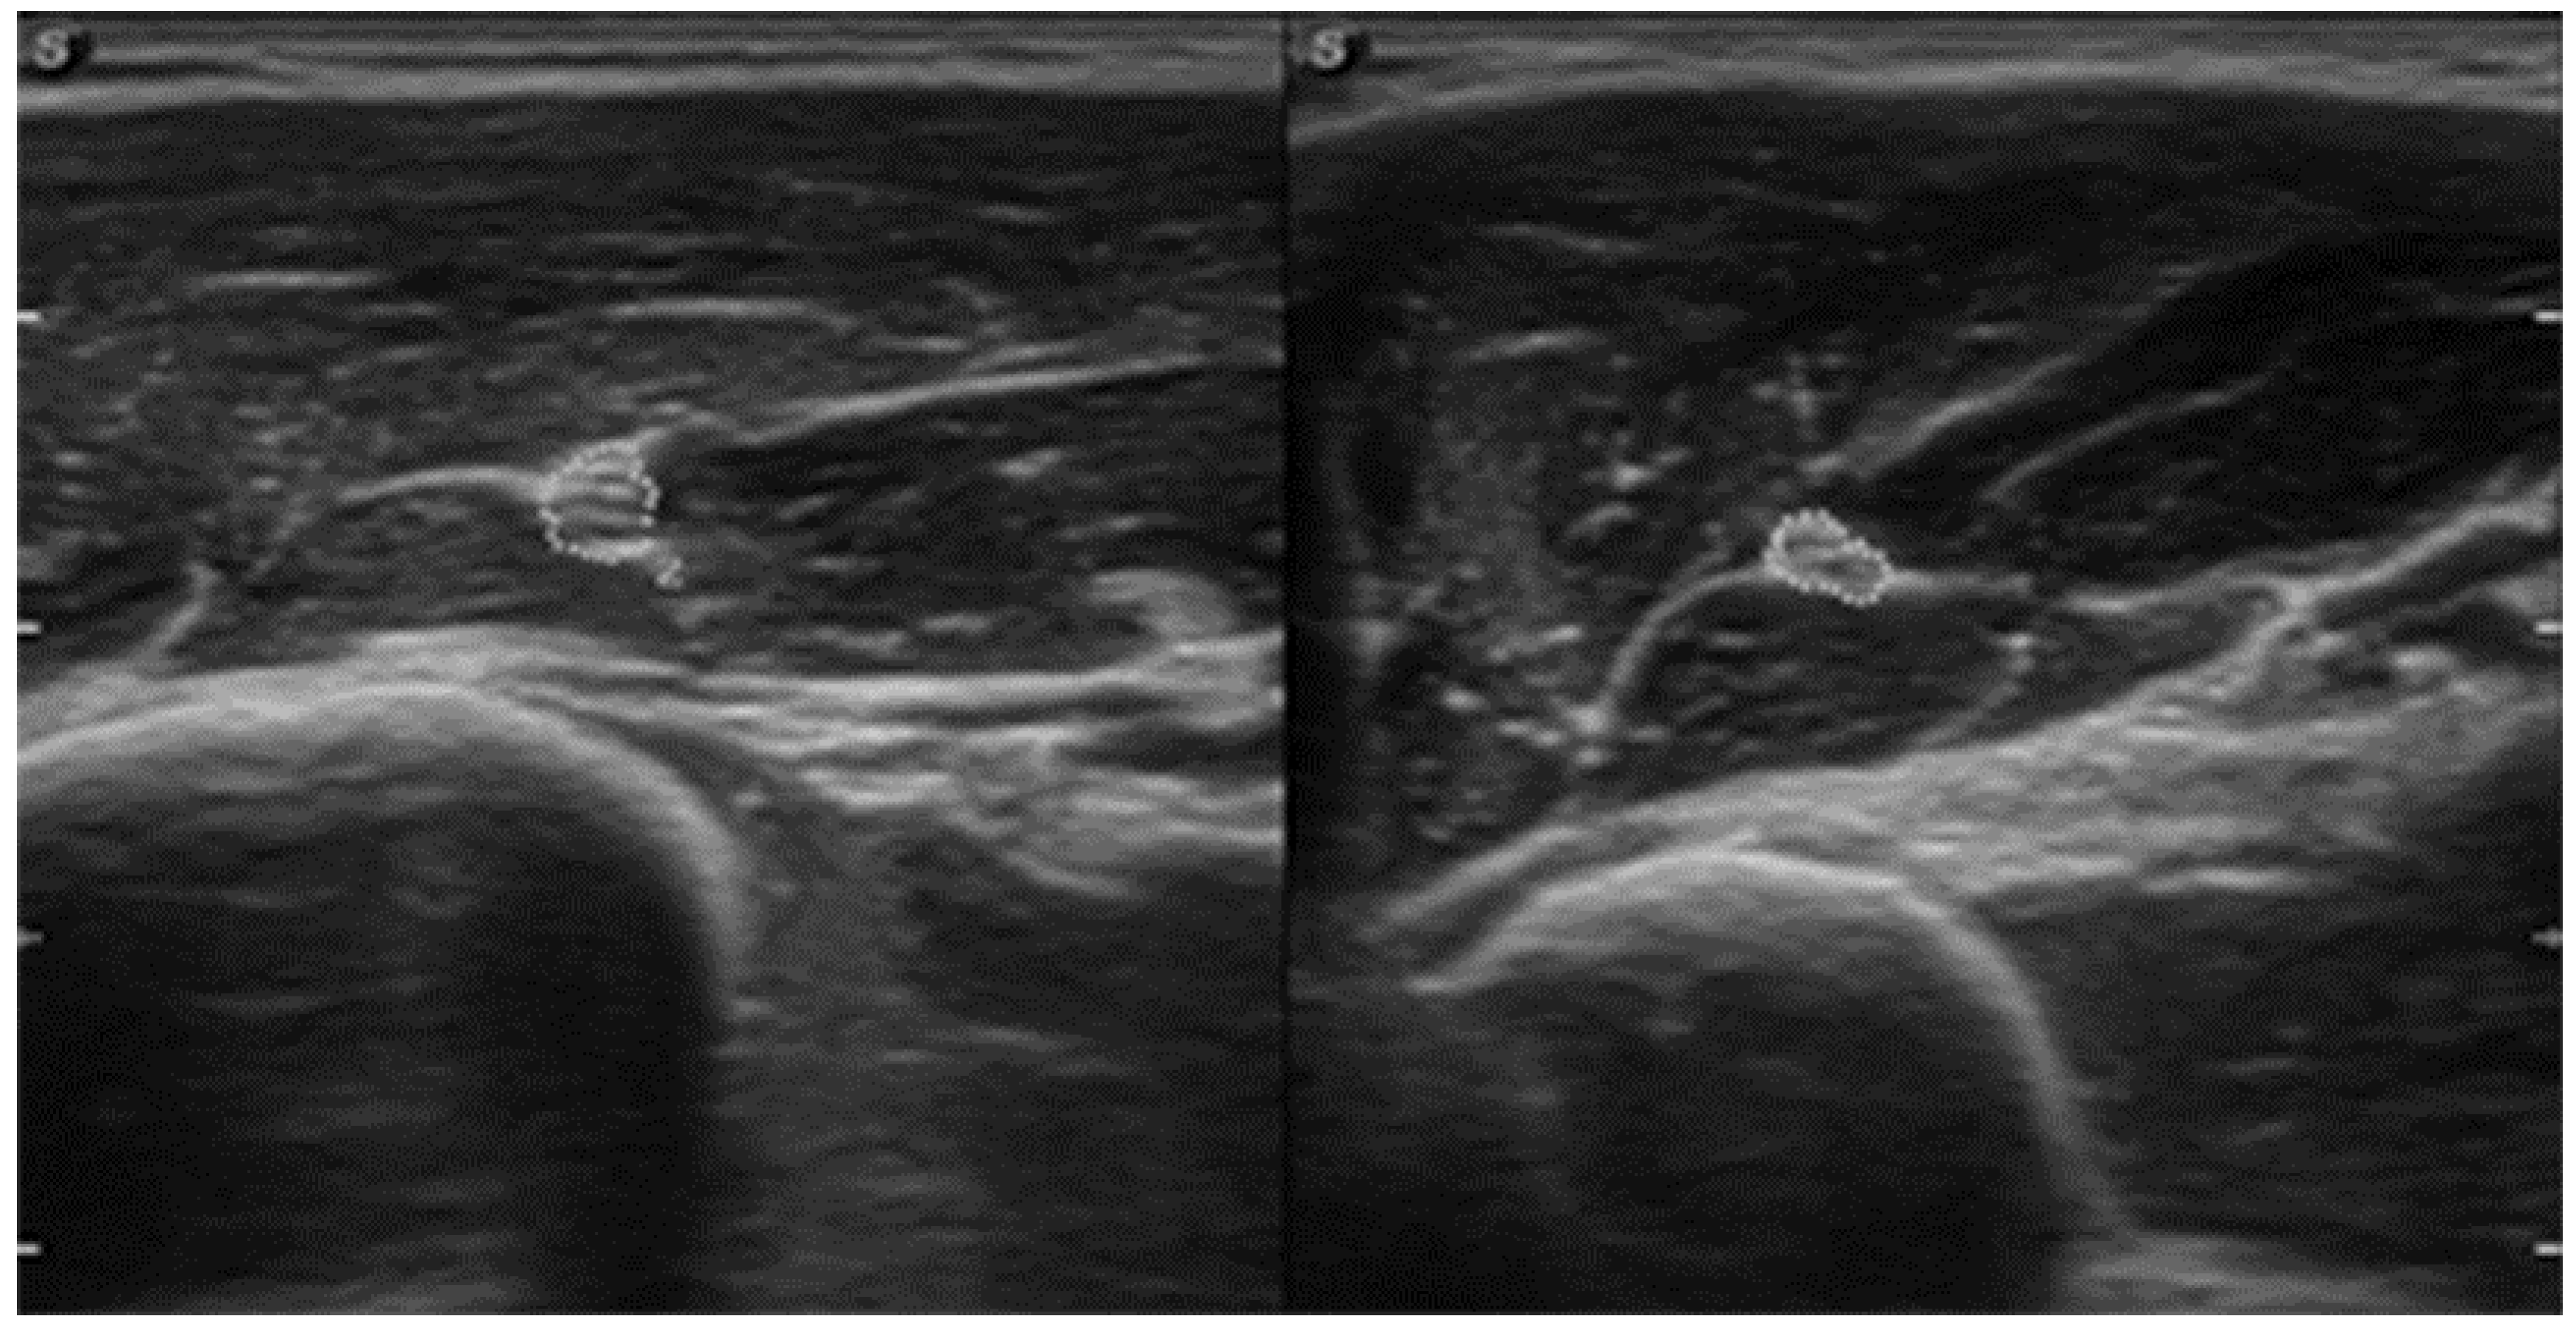

| July | Symptoms: brachialis muscle atrophy (Figure 1 and Figure 2) (pain 4/10 NPRS). Assessment: medical history, physical examination, ultrasound (orthopaedic surgeon). Diagnosis: unspecified soft tissue diseases associated with their use overload and overexertion (M70.9 ICD). Treatment: pharmacological treatment, avoid full weight-bearing. Effects: no positive therapeutic effect. |

| October | Symptoms: episodic of more severe pain, paraesthesia, tingling, numbness and burning sensations of right upper limb, (pain 3/10 NPRS). Assessment: medical history, physical examination (another orthopaedic surgeon), shoulder (Figure 3) and elbow MRI order (the same orthopaedic surgeon), cervical spine MRI order, electromyography, nerve conduction study (Table 2 and Table 3) (another orthopaedic surgeon), medical history, physical examination, ultrasound (another physiotherapist). Diagnosis: mononeuropathy of the upper limb, unspecified (G56.9 ICD) (orthopaedic surgeon), PTS suggestion (physiotherapist) Treatment: orthopedy surgeon: physiotherapy (massage, muscle relaxation, electrostimulation, exercises); physiotherapist recommendation: neurodynamic techniques. Effects: no positive effect. |